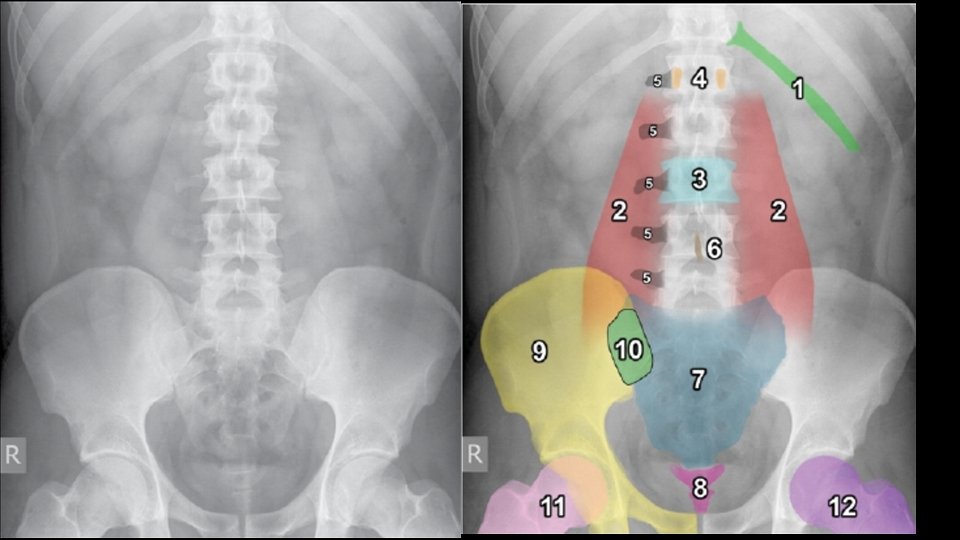

Abdominal viscera • Solid • • Liver Spleen Kidneys and adrenals Pancreas • Hollow • Stomach • Small bowel • Large bowel • Musculoskeletal parts

Normal Anatomy